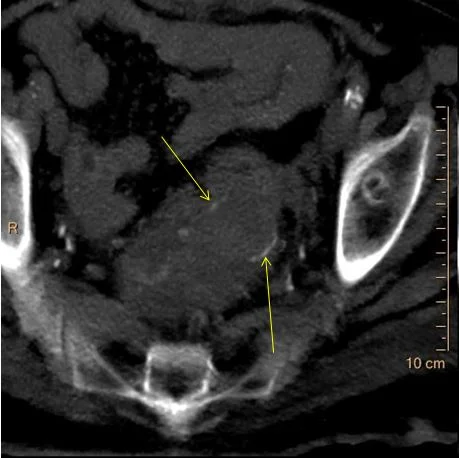

Conventional CT: Red arrow shows “hyperdensity” in the rectal lumen.

Virtual non-contrast: The “hyperdensity” is gone! So you do not really need a true non-contrast exam. The yellow arrows show the anastomosis.